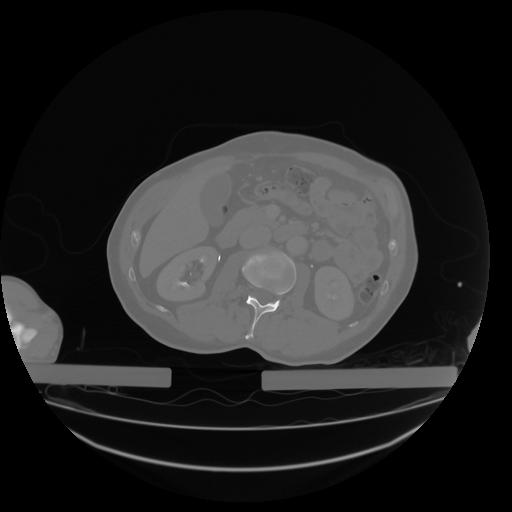

27 CUERPO,CE,Axial,3.0,CUERPO,,